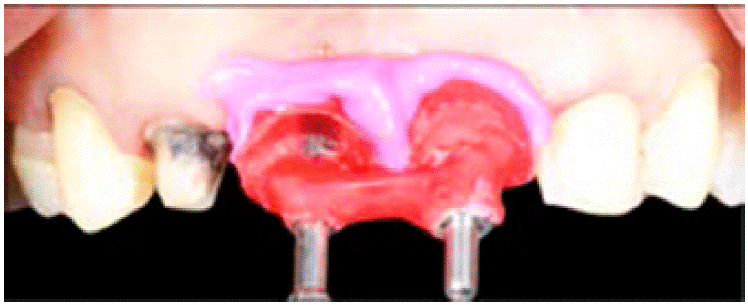

Una vez colocado el mock up y aceptado por la paciente, se individualiza la zona de los implantes 1.1, 2.1 para comenzar a manipular los tejidos con com presión y aumentos de resina en estos mismos.

El aumento de resina además del retiro y conexión de los provisionales en los centrales se realizó dependiendo de la respuesta de los tejidos, el aumento de resina se hizo milímetro a milímetro para evitar la compresión excesiva de los tejidos periimplantarios. Se va analizando la forma y el nicho del perfil de emergencia, logrando así un nicho de 3 mm de grosor, medida ideal para su conformación (Figuras 6y7).

Se retira el pilar provisional para unirlo a un análogo del implante e introducirlo en el polivinilsiloxano (Figuras 9y10).

Cuando el PVS termina de polimerizar se retira sólo el pilar de provisional y se coloca en su lugar un poste impresión. Alrededor de éste quedará el nicho correspondiente al perfil de emergencia donde colocamos resina acrílica (Figura 11).